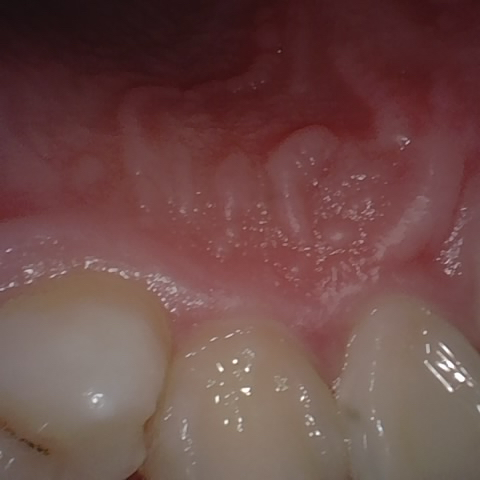

Annotated as "Good"